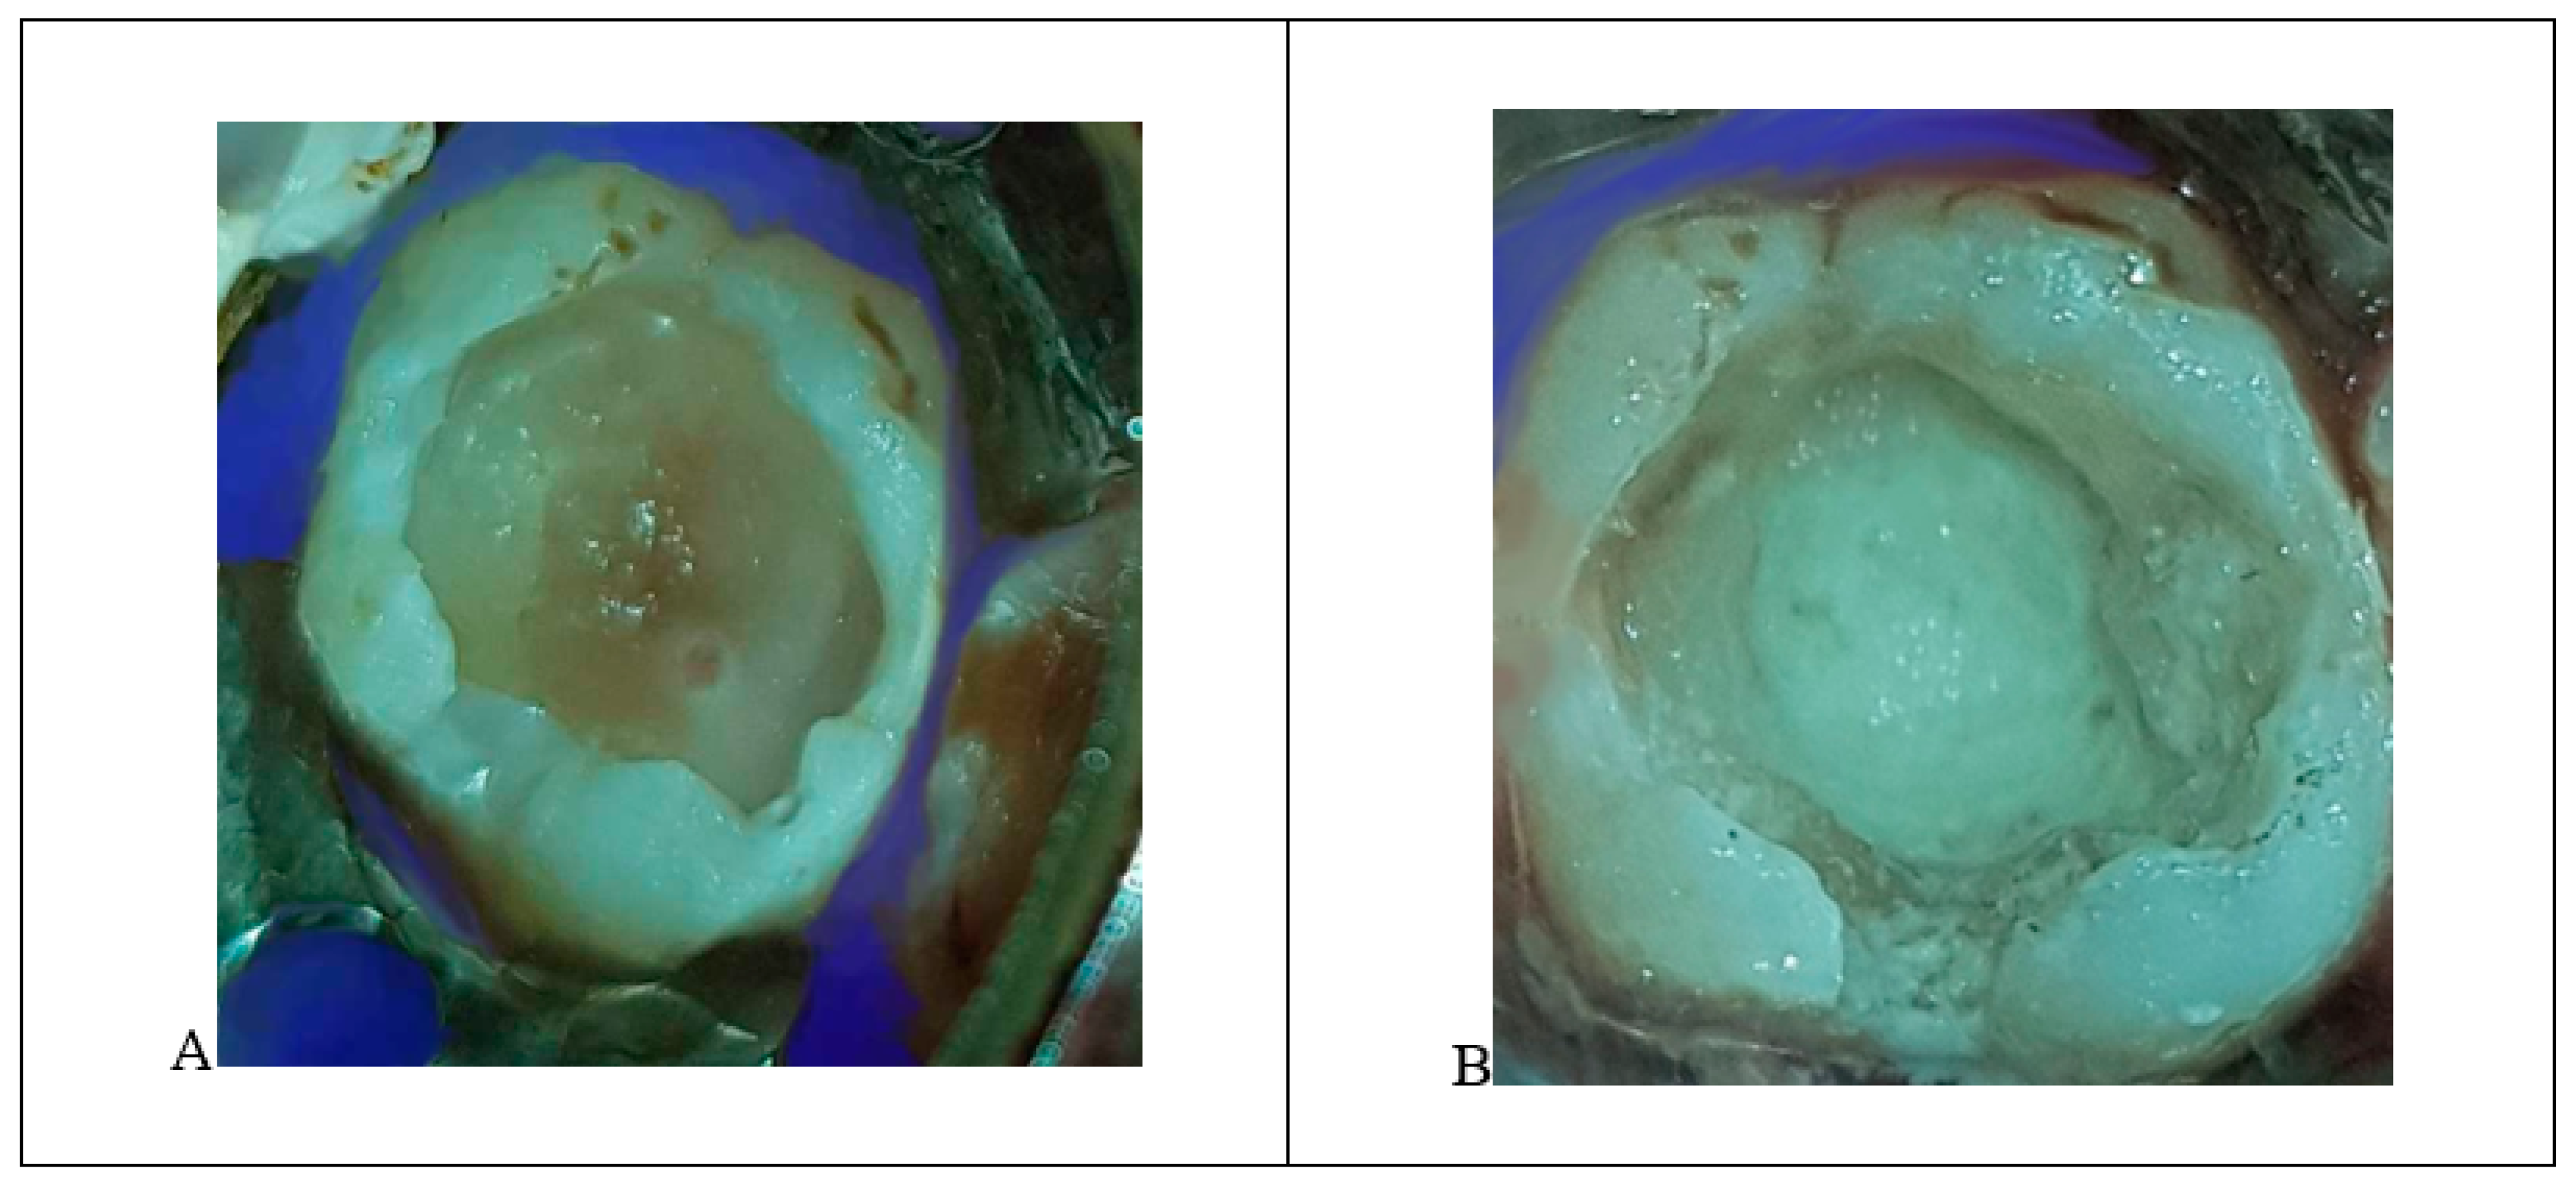

The upper-right first permanent molar (Tooth #16) had an asymptomatic deep carious lesion.

- The procedure involved local anesthesia and rubber dam isolation.

- A pinpoint pulp exposure happened (Figure 6A).

Figure 6. (A) A pinpoint pulp exposure in tooth #16. (B) MTA placed. - A coronal pulpotomy was completed by removal of coronal pulp tissue.

- Hemostasis was achieved using 5% sodium hypochlorite and MTA placed as a dressing material over pulp orifices (Figure 6B).

- The tooth was restored like teeth #36 and #46.